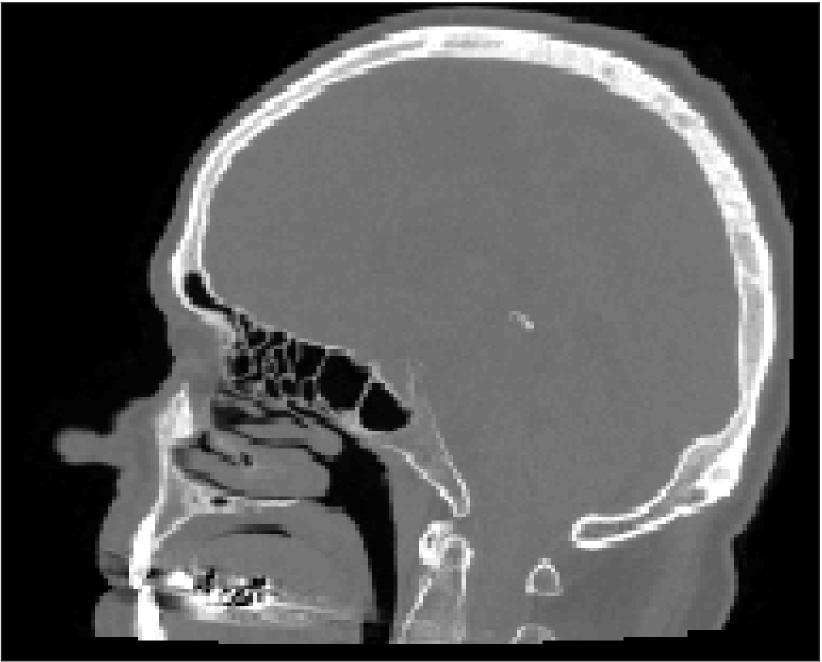

All MR images were acquired with a 1.5 T Siemens Espree scanner. The UTE images were reconstructed to 192×192×192192192192192\times 192\times 192 voxel bitmapped images with an isotropic resolution and a voxel size of 1.33 mm. The UTE sequences sampled the k-space radially with 30 000 radial spokes. CT images were acquired with a tube voltage of between 120 kV and 130 kV on either a GE Lightspeed Plus, Siemens Emotion 6 or GE Discovery 690. The in-plane pixel size varied between 0.48 mm to 1.36 mm and the slice thickness between 2.5 mm and 3.75 mm. Images of the same patient were co-registered and resampled to achieve voxel-wise correspondence between all five modes. A binary mask excluding most of the air surrounding the head was computed from the images and used to remove unnecessary data. Furthermore, to reduce the execution time of the parameter estimation phase, only 11 slices in the middle of the head of each patient was used during the parameter estimation phase, but all slices were used during the prediction phase (s-CT generation). Additional details concerning the data can be found in Johansson et al. [16]. Data from one slice of a patient is shown in Figure 3.

Refer to caption

(a) Binary mask

(b) CT

(c) First echo, 10superscript1010^{\circ}

(d) Second echo, 10superscript1010^{\circ}

(e) First echo, 30superscript3030^{\circ}

(f) Second echo, 30superscript3030^{\circ}

Figure 3: Binary data mask (panel a), CT image (panel b), The four MRI UTE sequences (panels c-f).